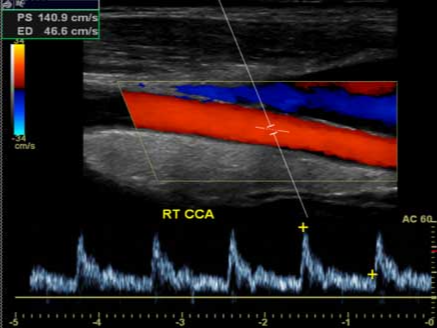

경동맥 초음파 검사는 목 양쪽을 따라 흐르는 주요 혈관인 경동맥의 상태를 실시간으로 확인할 수 있는 대표적인 혈관 검사입니다. 초음파를 이용하기 때문에 방사선 노출이 없고, 시술이 간단하며, 통증이 거의 없어 많은 분들이 건강검진에서 함께 진행하고 있습니다. 특히 심뇌혈관 질환 위험이 증가하는 40대 이후, 고혈압이나 당뇨 등 만성질환이 있는 분들, 흡연자, 가족력이 있는 분들에게 조기 진단과 예방을 위해 권장되는 검사입니다. 경동맥 내부에 혈전이나 플라크가 쌓여 혈관이 좁아지거나 딱딱해지는 이상 소견은 뇌졸중 위험 증가와 직결될 수 있어 빠르게 확인하고 관리하는 것이 무엇보다 중요합니다.

경동맥 협착증은 혈관이 좁아진 정도를 퍼센티지로 산출하여 뇌로 가는 혈류의 장애 정도를 판단할 수 있습니다.

동맥경화가 심해져 플라크가 형성되면, 작은 조각이 떨어져 나가 뇌혈관을 막으면서 허혈성 뇌졸중을 유발할 수 있습니다. 따라서 플라크 유무와 상태 파악은 예방 측면에서 매우 중요합니다. 내막 두께(IMT)는 혈관 노화 지표로, 정상치보다 두꺼워지면 심혈관 질환 발병 위험 증가를 시사합니다. 특히 당뇨병, 고혈압 환자에게서 흔히 관찰되므로 관리의 기준이 됩니다. 드물지만 동맥류나 박리 등 혈관 벽 질환도 파악할 수 있어 응급상황 예방에 도움을 줍니다. 눈으로 직접 보이지 않는 혈관이기 때문에 초음파 영상으로 구조와 흐름을 동시에 평가할 수 있다는 것이 큰 장점입니다.

- 혈관 내막 두께, 혈류 속도, 플라크 여부 등 확인